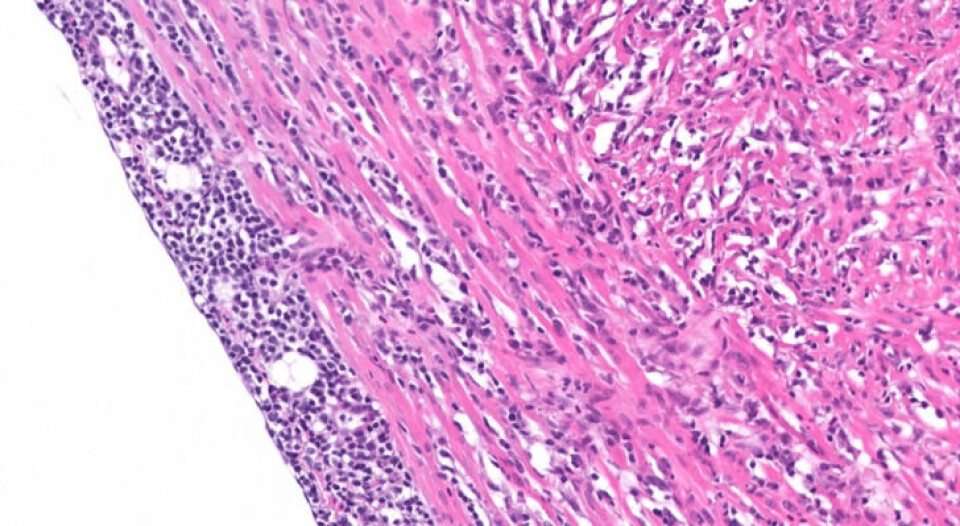

PRV-vaksinen reduserte betydelig mengden med PRV-virus og histopatologiske lesjoner som er typiske for HSMB, sammenlignet med den uvaksinerte kontrollgruppen. Dette er den første dokumentasjonen av beskyttende vaksinasjon mot PRV, og lovende for fremtidig kontroll av HSMB i atlantisk laks.